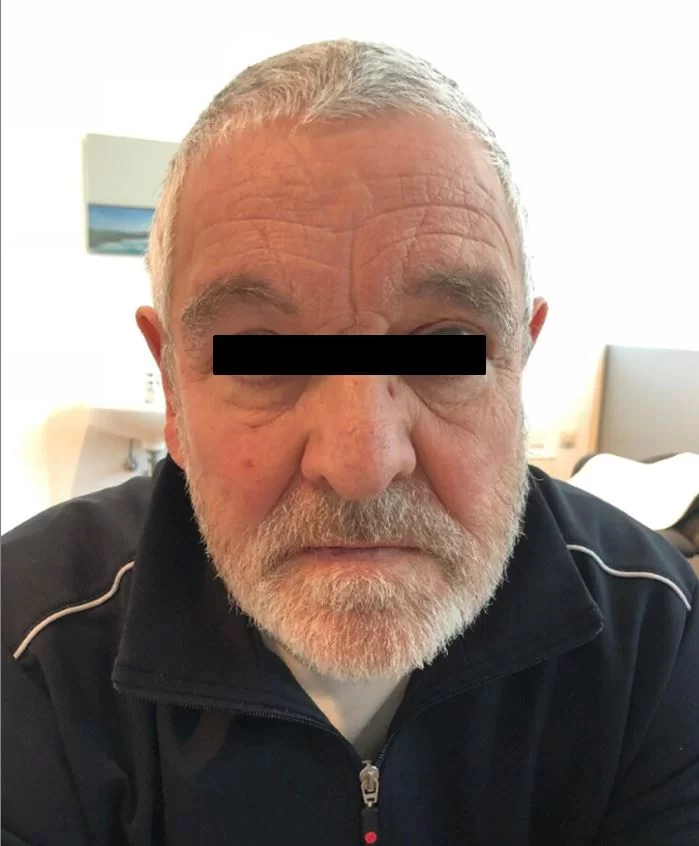

Διενεργήθη δεξιά υπερκόγχιος κρανιοτομία (τομή στο φρύδι) και ολική εξαίρεση της βλάβης.

Οι ελάχιστα επεμβατικές τεχνικές (όπως για παράδειγμα η κρανιοτομία δίκην κλειδαρότρυπας) προσφέρουν πολλά πλεονεκτήματα σε σχέση με τις κλασσικές μεθόδους και άριστο αισθητικό αποτέλεσμα. Το συγκεκριμένο περιστατικό αποδεικνύει ότι ακόμα και μεγάλοι όγκοι της βάσης του κρανίου μπορούν να αφαιρεθούν με ελάχιστα επεμβατικές τεχνικές.